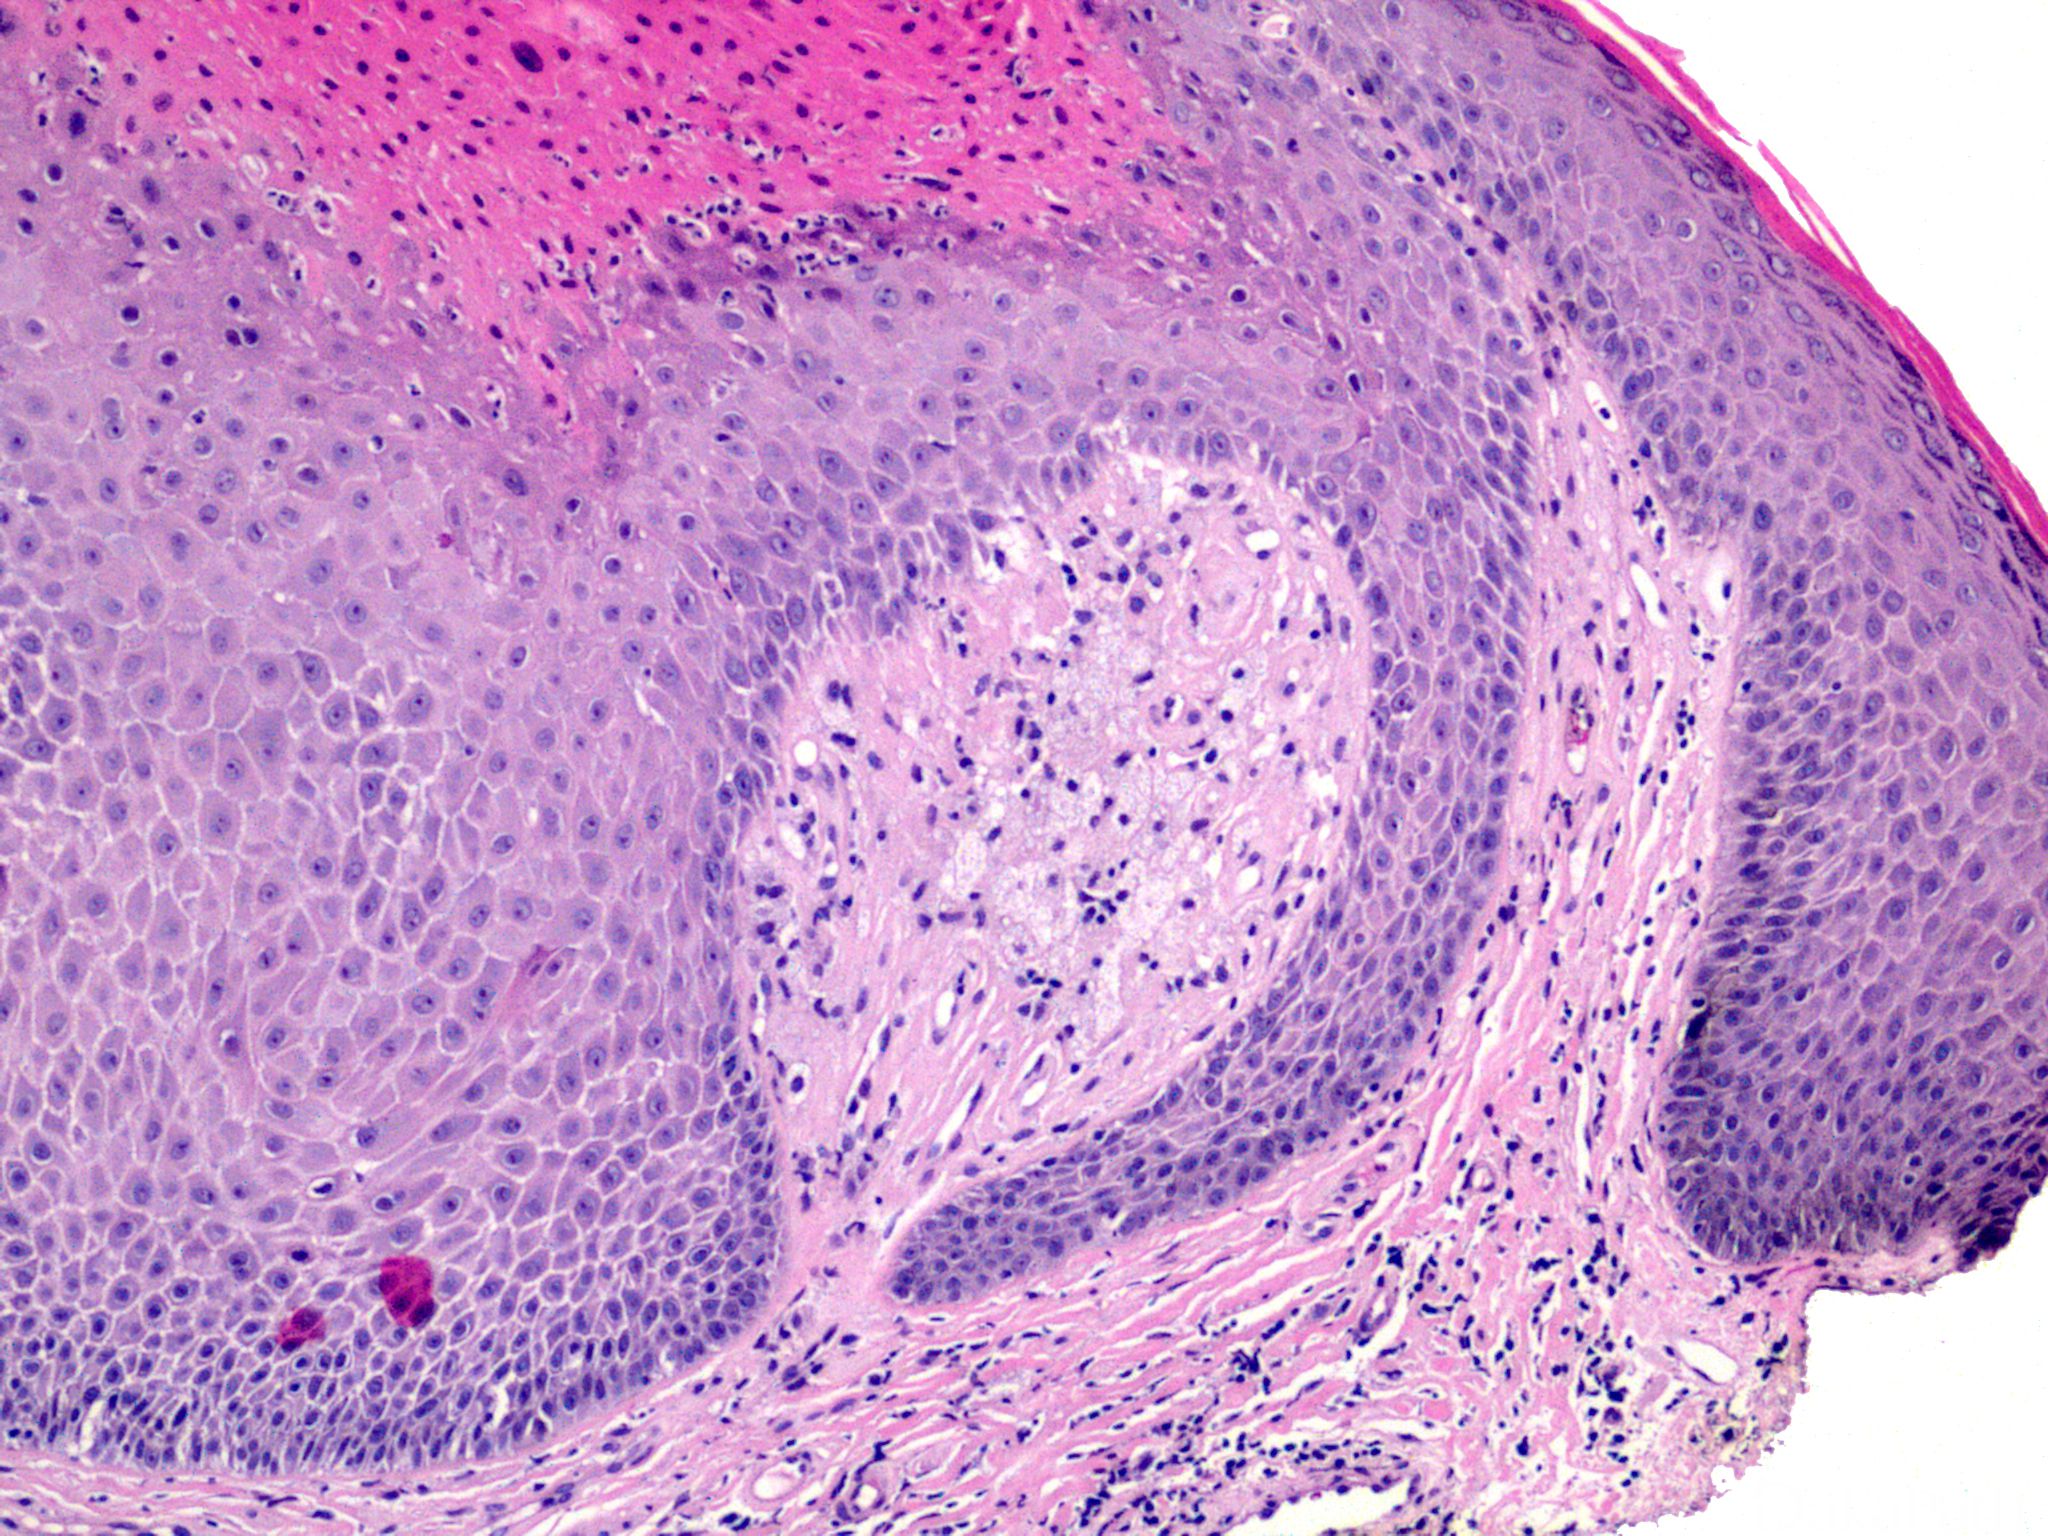

疣状黄瘤

verruciform xanthoma